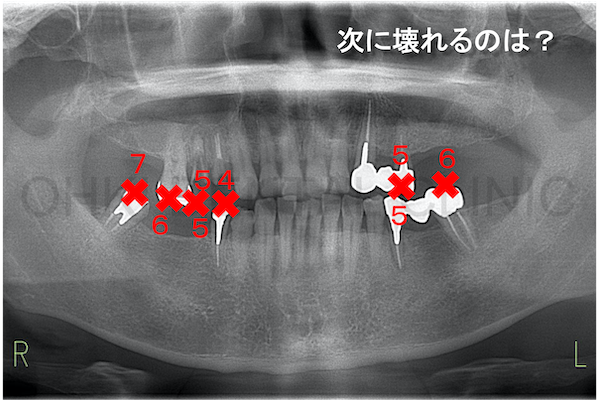

歯が悪くなる原因には虫歯、歯周病、噛み合わせの3つがあります。

虫歯や歯周病によって歯を失うと、噛み合わせのバランスが崩れて様々なトラブルが生じます。早めに治療を行いこれ以上のトラブルが起きないようにしておかないと、どんどんお口の中が崩壊していきます。

特に一番後ろの歯には最も負担がかかります。崩壊を食い止めるためには、いかに力の分散を行い、歯1本1本にかかる負担を軽減するかが大切です。

全顎治療が必要になる場合のほとんどは噛み合わせのバランスが崩れている患者様です。